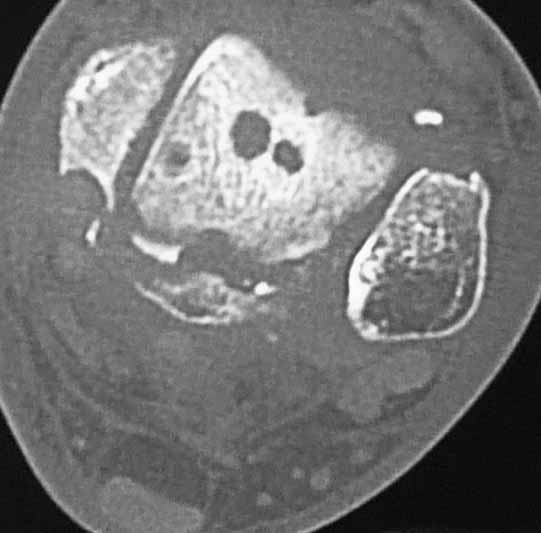

Уважаемые коллеги. Не так давно на форуме коротко обсуждались возможные последствия

трансартикулярной фиксации голеностопного сустава при переломовывихах лодыжек.

На днях довелось увидеть КТ после удаления спиц. Картинки наглядные и, практически, не

нуждаются в комментариях. Одна из спиц, кстати, проходила через фрагмент заднего края.